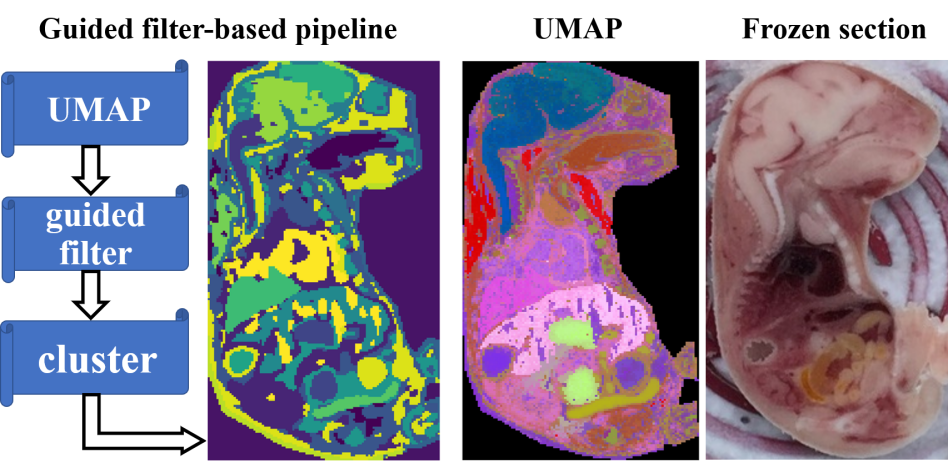

该研究工作使用脂质体特征的小鼠胎儿质谱成像数据,比较新的分割流程与其他常用的三种流程的空间分割结果。结果说明,新流程能够更好地区分图像中的亚组织/微区,在目视检测、空间均匀性、时间成本和鲁棒性等方面均优于其他传统方法,如图1 所示。这项研究提高MSI的空间分割效果,为研究人员评估和筛选药物/化学诱导的靶向器官,探索疾病进展和分子机制提供了有力的工具。

图1. 小鼠胎儿分析结果。(左) 基于导向滤波的分割流程及结果;(中) UMAP降维结果; (右) 冷冻切片。